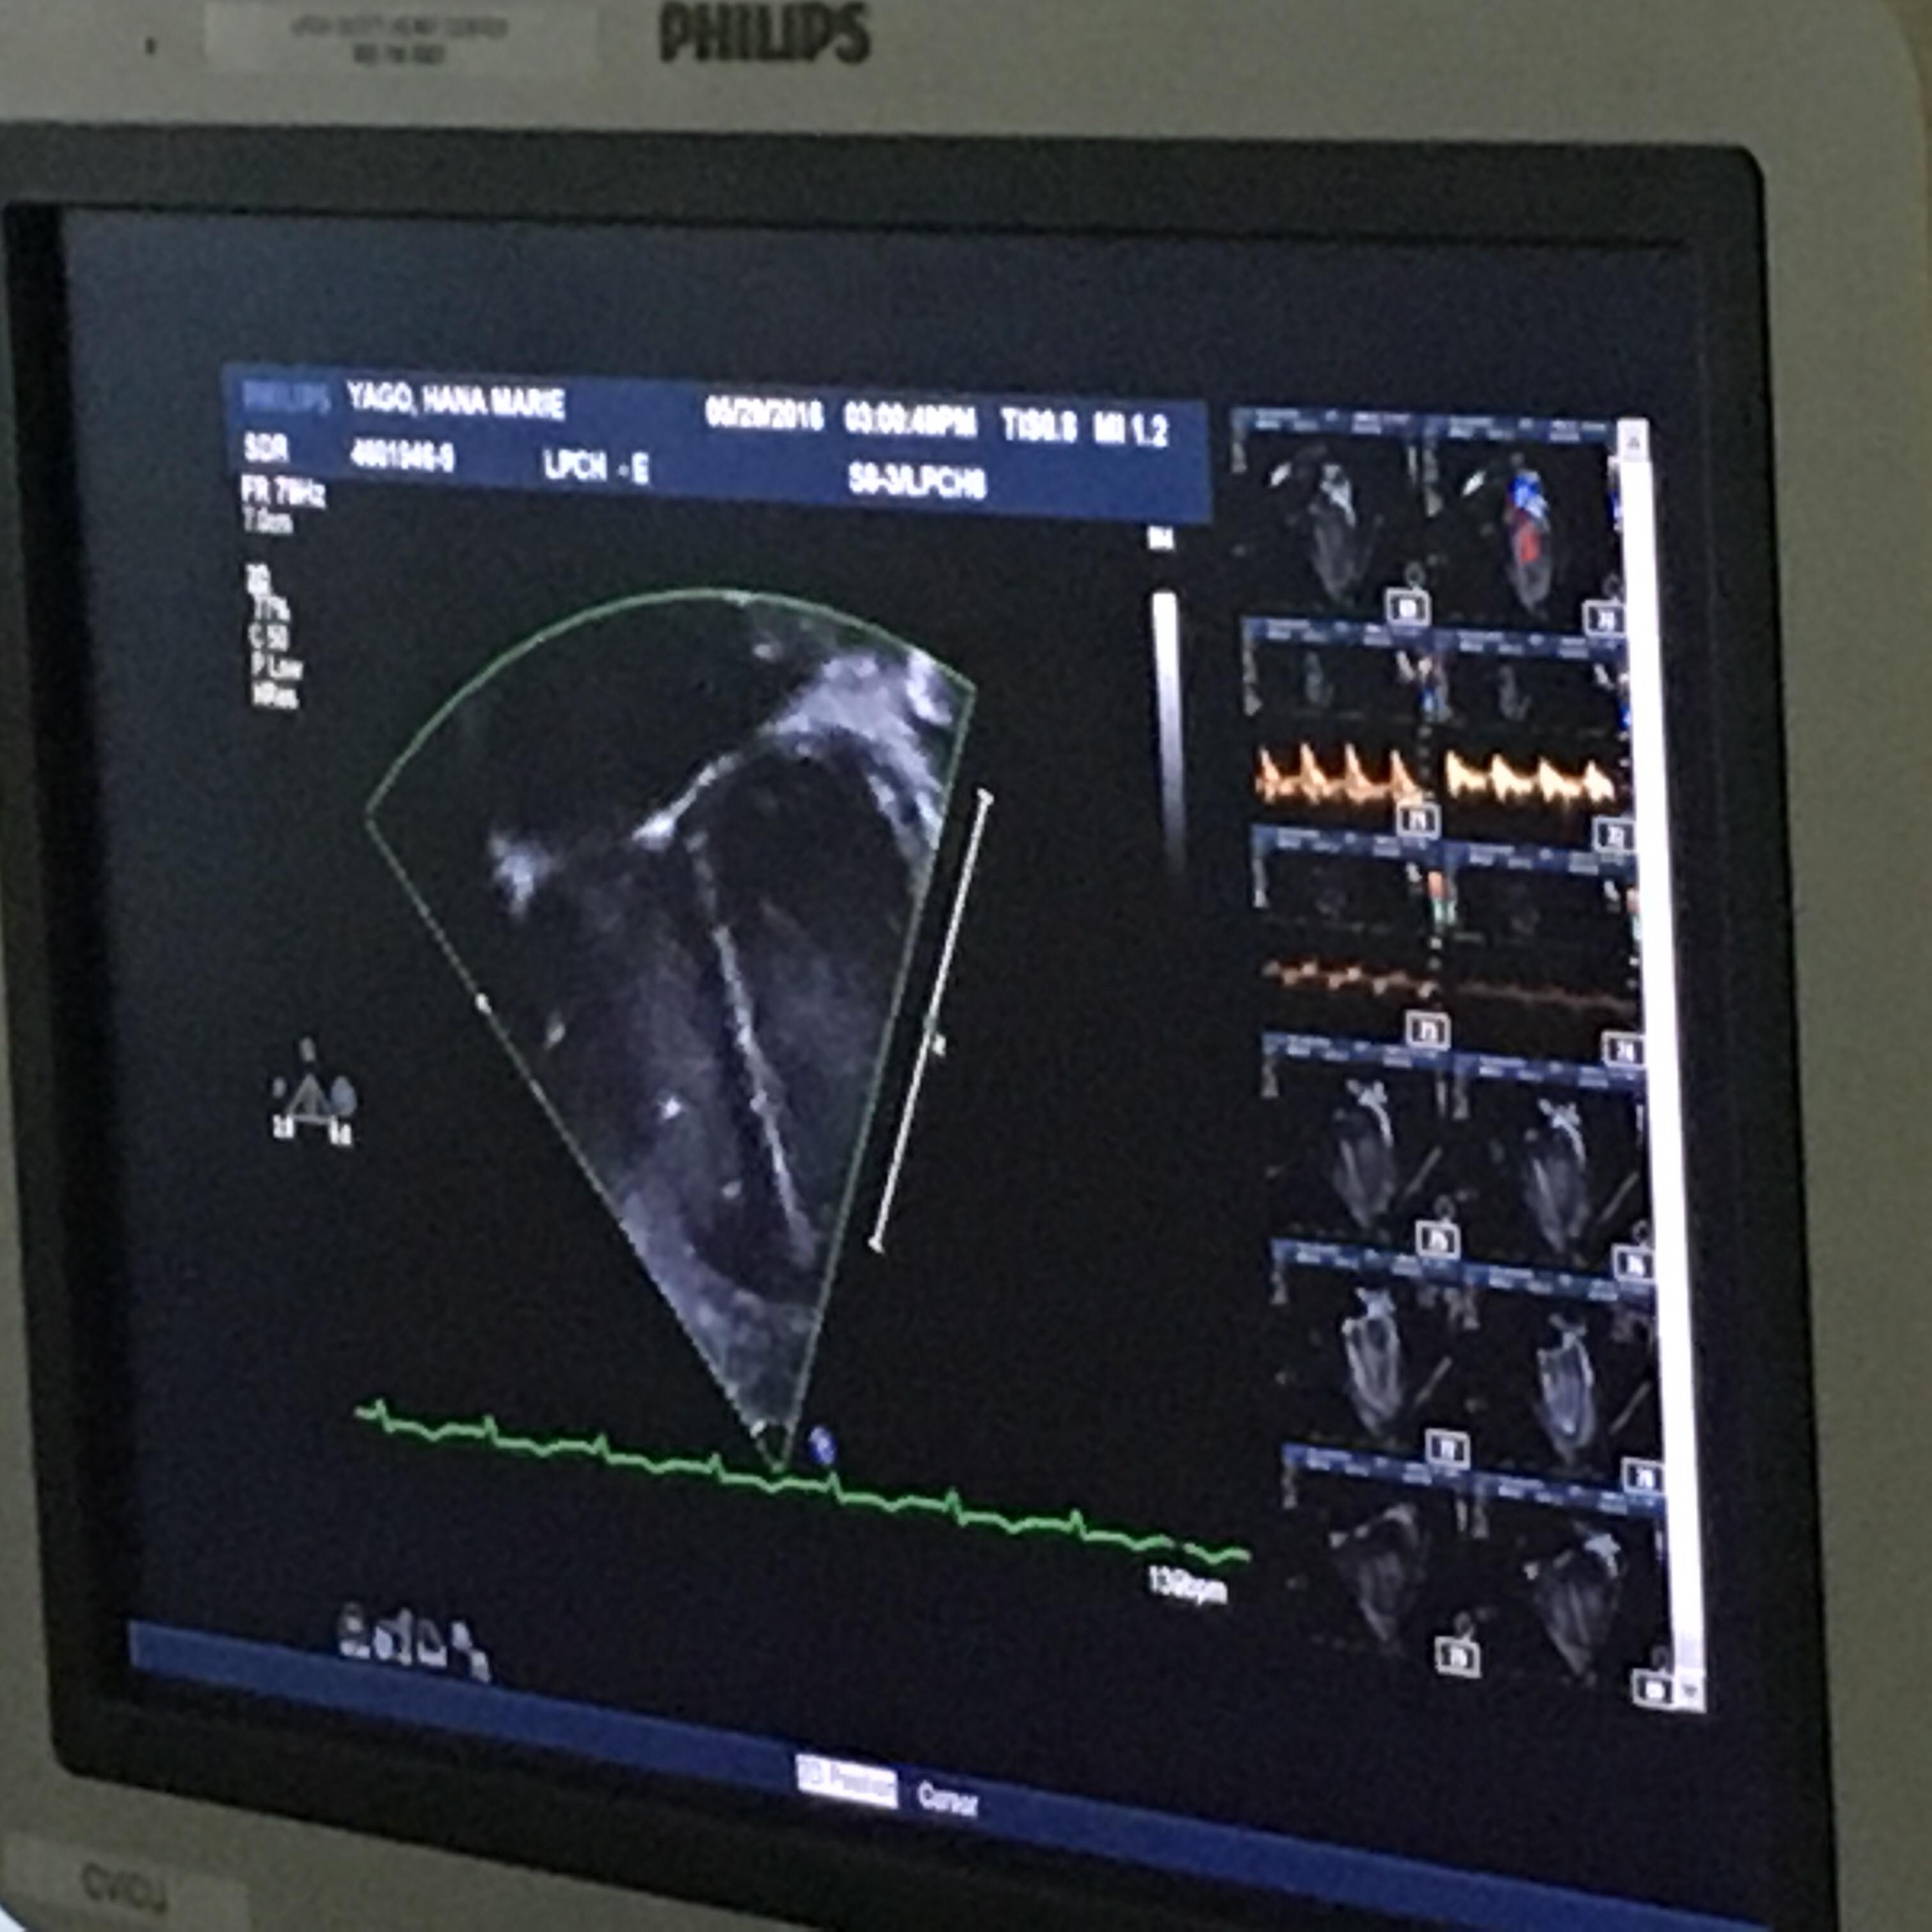

Everything is going really great. They have things they are “concerned” about which just means they watch and make adjustments for, but overall they are not concerned and they think she is doing great. Some “concerns” are her CVPs (central venous pressure) which have been high around 14. They want it to be closer to 10. This means there is more pressure on the right side of her heart. This is why she is getting Lasix to offload fluid. In addition, they have her hooked up to a pacemaker. Her heart rate is set to 140. Her blood pressure was low, due to the precedex but is coming up nicely now that they’ve taken her off of it.

Her right heart they are watching closely because of a long ischemic time. This means her new heart was without oxygen for a long time, although within acceptable limits for a transplant. This happened because her new heart came from “further away”. They can’t tell us anything about the donor but this tidbit of information came up because it is part of Hana’s care. She also might need to be on milrinone for the same reason. If her CVPs don’t come down by this afternoon then they will do an echocardiogram.